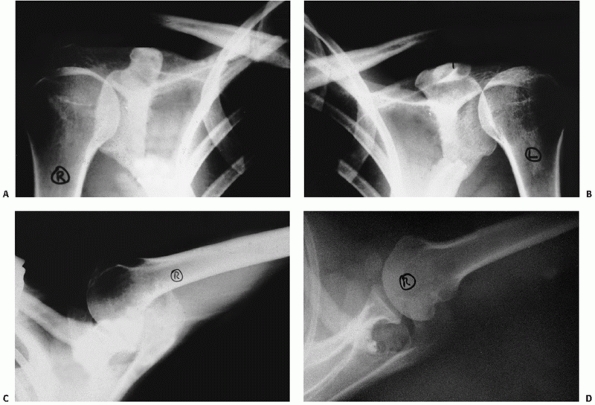

FIGURE 39-10

Radiographs of a patient with a type III variant injury involving the AC joint and a fracture of both the base and the tip of the coracoid. A. An anteroposterior radiograph of the injured right side. The coracoid injury is not visualized. B. A radiograph of the uninjured left side demonstrating that the coracoclavicular distance is equal on the injured and unaffected sides. C. An axillary view shows the tip fracture, but the fracture at the base is not easily detected. D. The West Point view clearly shows the fracture at the tip of the coracoid process. (continues) |

![]() |

|

FIGURE 39-10 (continued) E. The Stryker notch view clearly shows the fracture at the base of the coracoid. F. Nonoperative treatment in this case led to an excellent result as evidenced by full overhead elevation. G. The patient regained near-normal internal rotation.